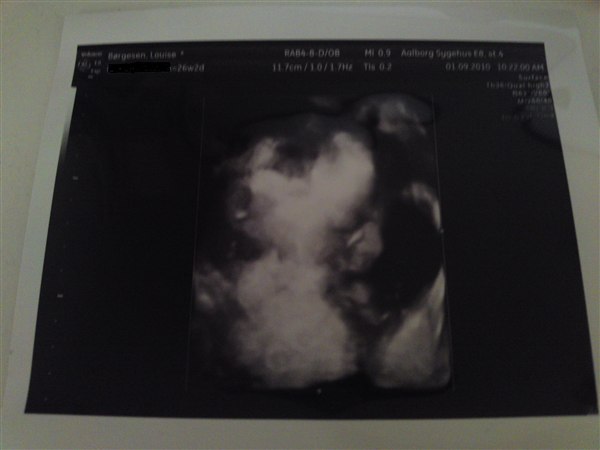

Det gik bare så godt idag til scanning, havde min mor med for første gang hun syntes det var utrolig spændende. Hvor er de vokset hurtigt for 3 uger siden vejde mine drenge kun 566g og 610g og nu vejer de 1017g og 1020g

Det er over 100g om ugen de har taget på, syntes det er vildt. fik også et rigtig fint 3d billede af den ene twin. Simpelthen en dejlig lille nus. glæder mig til at vise min kæreste det når han kommer hjem. Er bare overlykkelig for mine to drenge de følges så godt ad. Fik også svar på at det var for børnenes skyld at de anbefaler kejsersnit fordi de havde fundet ud af at de kunne stjæle vigtige ting fra hinanden under fødslen, nok ilt og nærring!! er ik helt sikker men er ret sikker på jeg bestemte mig for at kejsersnit så er ok når det er det der er bedst for børnene i det her tilfælde. Så må jeg så prøve en vaginal fødsel om nogle år hvis vi bestemmer os for enednu en bebs.